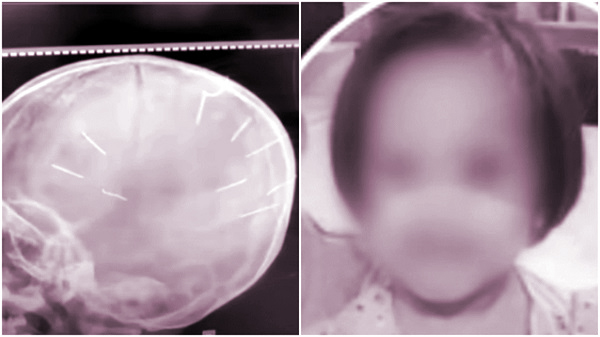

Hình ảnh cháu bé Đ.N.A với những chiếc đinh bị bắn trên đầu

Theo đó, Huyên sống chug với chị L và cháu Đ.N.A (3 tuổi, con riêng của chị L và người chồng trước). Thay vì yêu thương, chăm sóc trẻ, Huyên đã nhiều lần hành hạ cháu bé một cách tàn nhẫn như cho uống thuốc trừ sâu, nuốt đinh ốc vít, đánh gãy tay, đóng đinh vào đầu cháu… Sau nhiều ngày tích cực chữa trị, cháu A đã không qua khỏi.